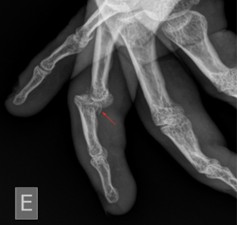

Image 2: Magnification of the X-ray above demonstrates an avulsion fracture of the base of the phalanx, indicating a volar plate avulsion fracture. Case courtesy of Leonardo Lustosa, Radiopaedia.org, rID: 99559

Volar plate injuries, including avulsion or oblique fractures into the PIP joint, are commonly seen with dorsal PIP dislocations. This injury warrants careful consideration in any patient with a history of a hyperextension mechanism injury to any digit. This will often be reported as having a “jammed” finger when playing contact sports or attempting to catch/corral a ball.3 Volar plate fractures involving greater than 30% of the articular surface may no longer be stable and may require surgical fixation. These warrant timely follow-up with hand surgery.3,4 If left untreated, dorsal dislocations and volar plate injuries can result in a persistent swan neck deformity. Irreducible dorsal dislocations, while rare, should prompt concern for an interposed volar plate. These require prompt orthopedic consultation for open reduction.5 Central slip extensor tendon injuries can be seen with volar PIP dislocations and can result in a Boutonniere deformity if missed or left untreated.4